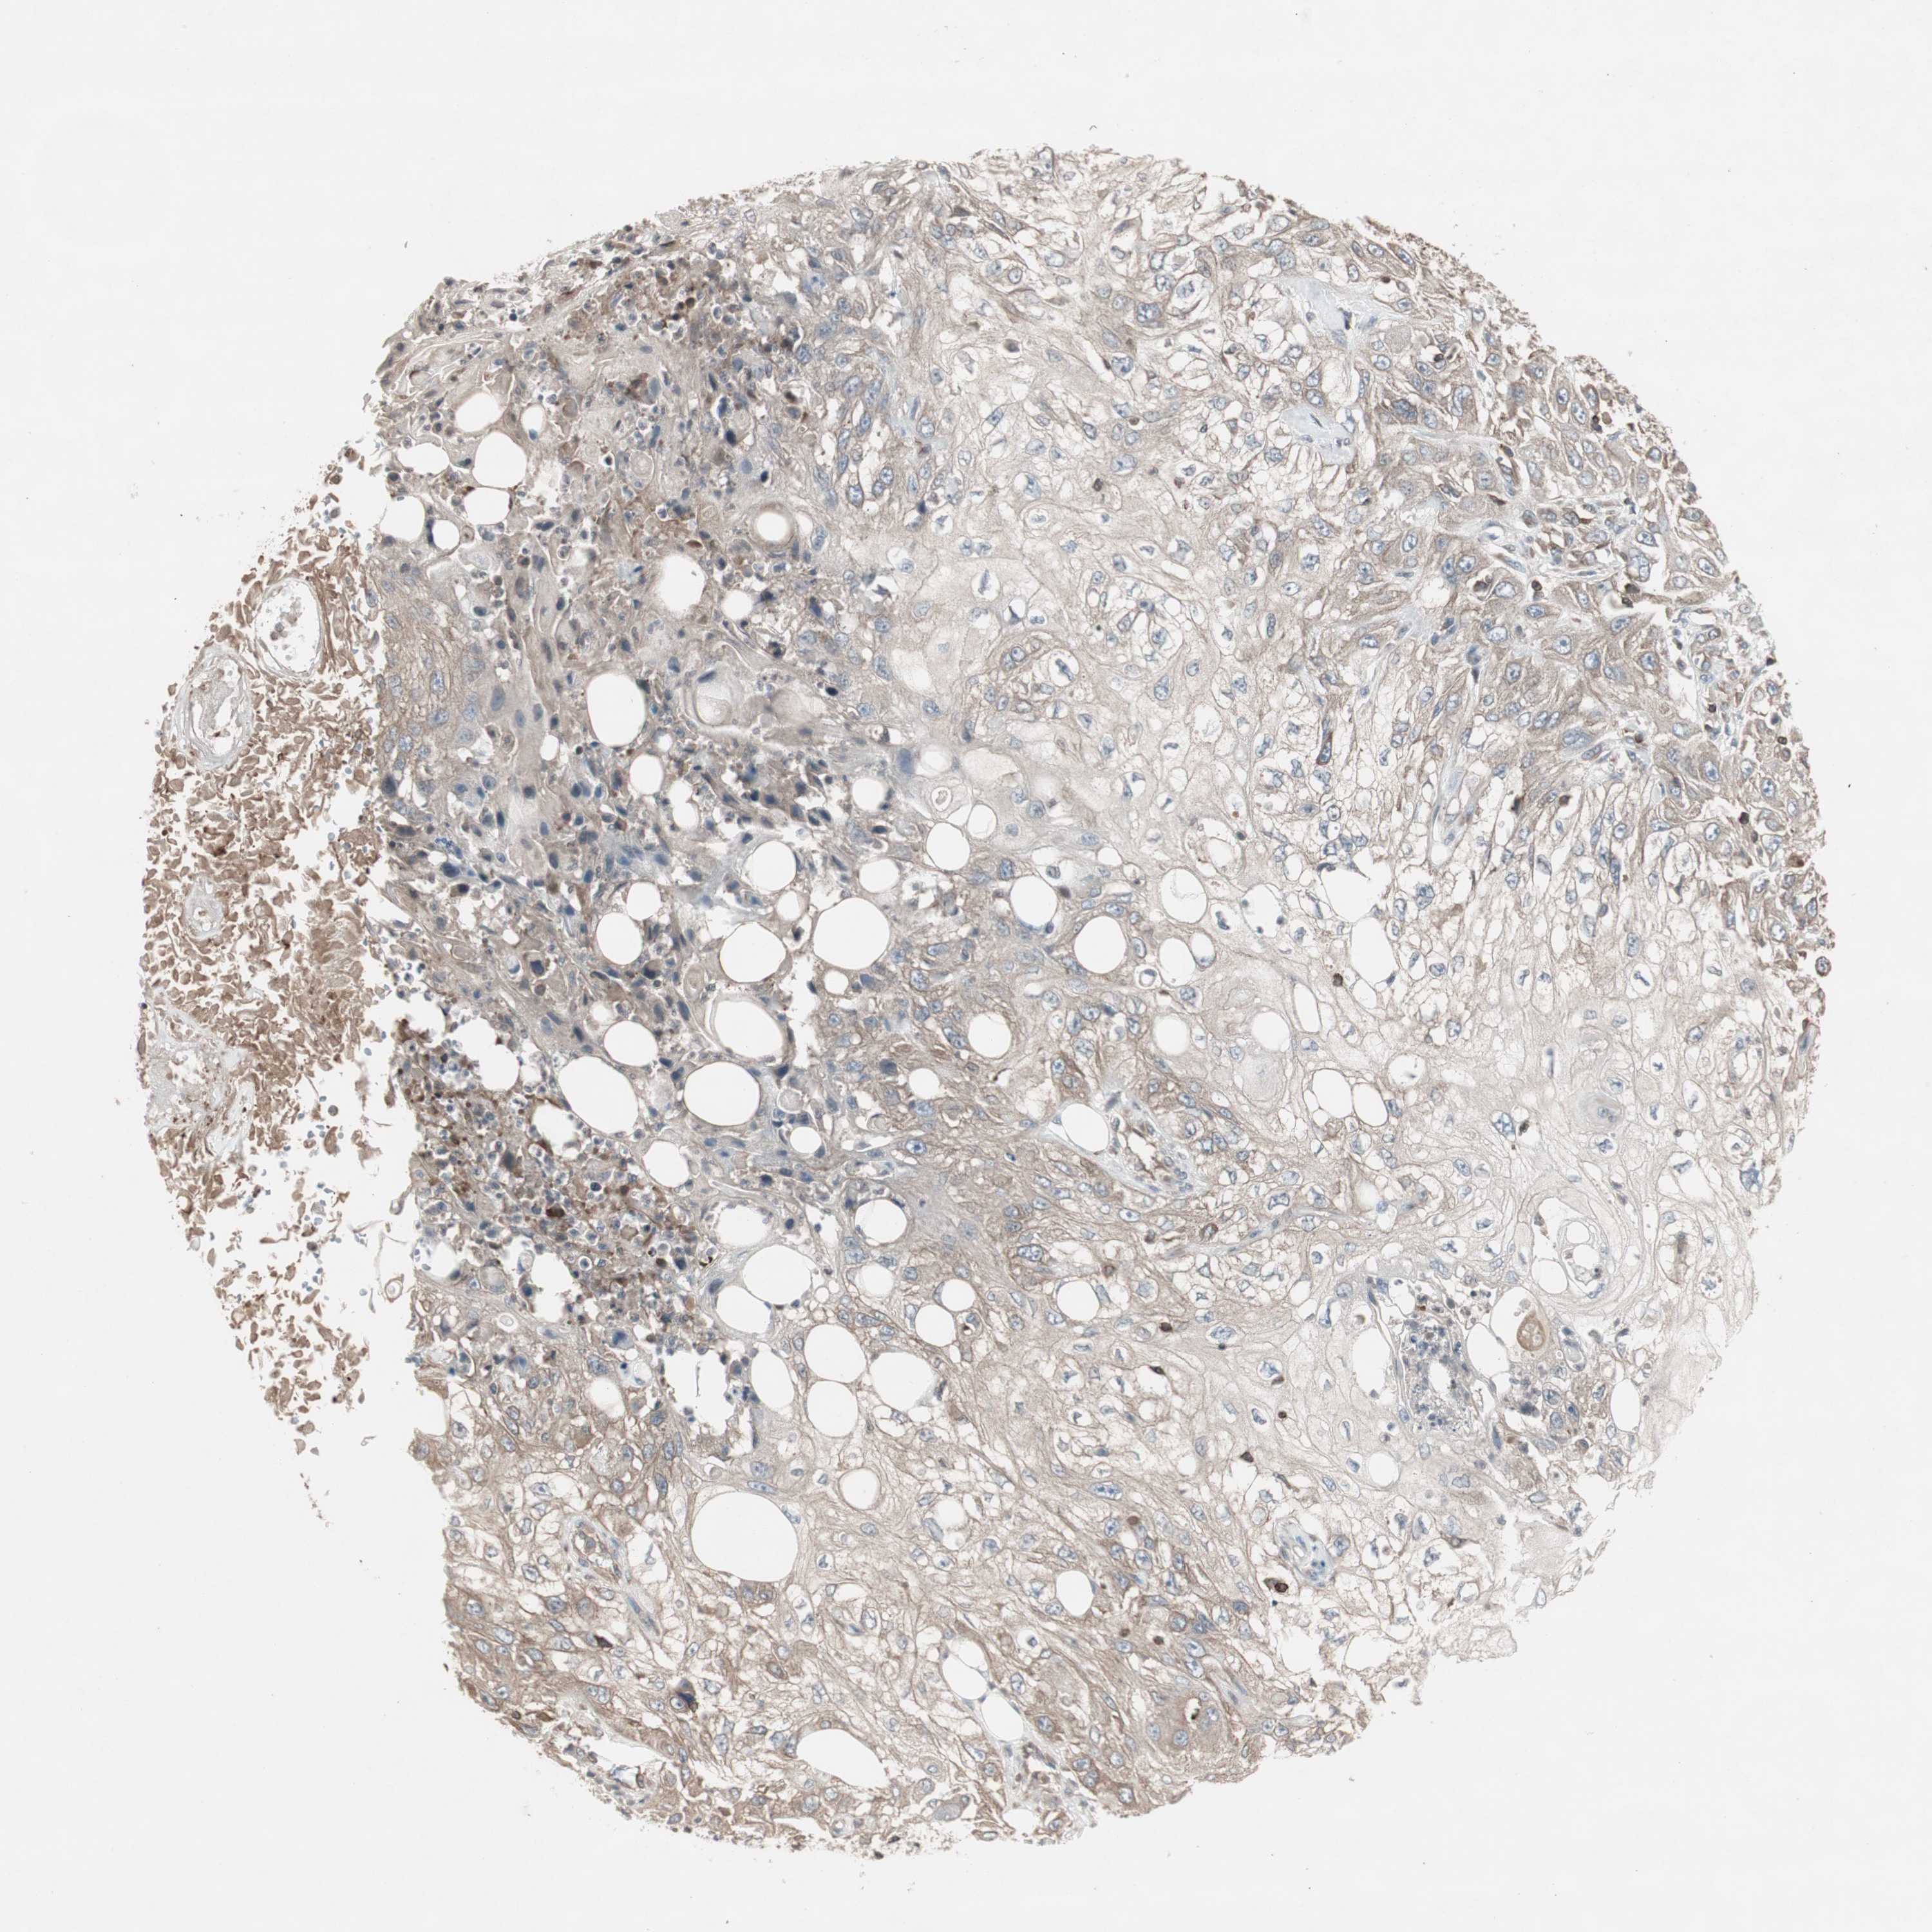

Basal cell and squamous cell cancer

SKIN CANCER - Protein expressioni

A mouse-over function shows sample information and annotation data. Click on an image to view it in a full screen mode. Samples can be filtered based on level of antibody staining by selecting one or several of the following categories: high, medium, low and not detected. The assay and annotation is described here.

Each image is clickable and will lead to virtual microscopy that enables deeper exploration of all samples and also displays staining intensity scores, fraction scores and subcellular localization as well as patient and tissue information for each sample.

Antibody CAB009502

Adnexal tumor, benign